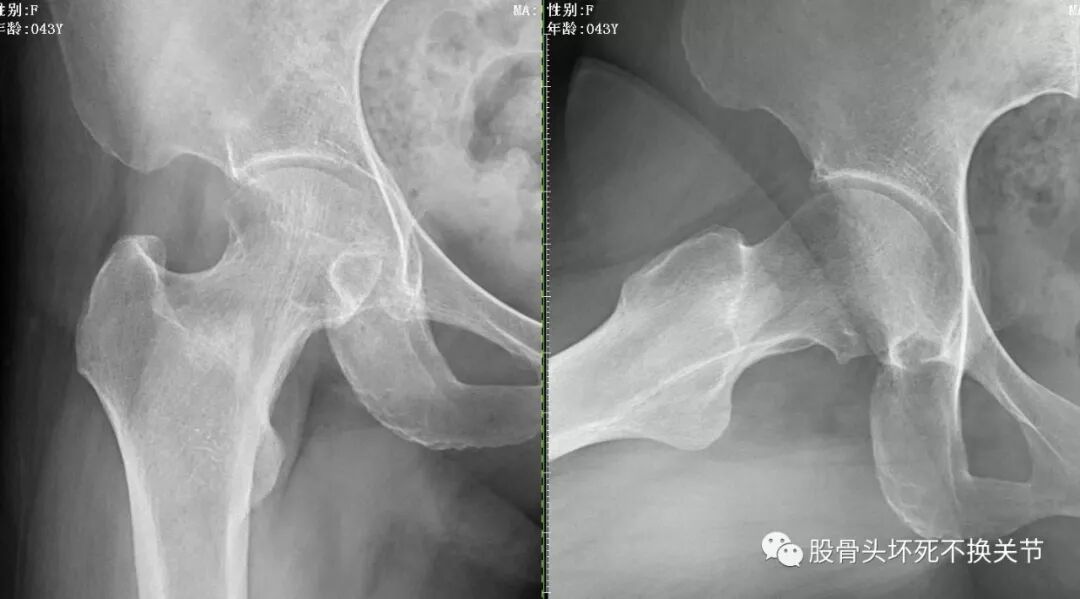

右髋特写

从这些歪斜的X线片子可以看到,双髋关节并无特殊表现,双侧骶髂关节似乎轻微硬化(对于42岁生过孩子的女性来讲,不首先考虑病理原因);仔细研判放大了的右髋关节正位、蛙位片,可发现股骨头边缘轮廓并不是特别光整,与对侧相比右侧股骨近端整体骨密度低于对侧,对于一个长期患病、缺乏活动的关节来讲,不足为道,很常见。